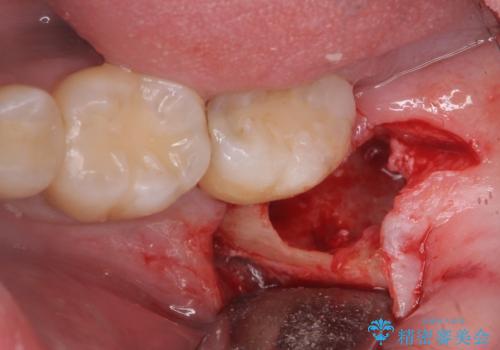

親知らず抜歯

- 親知らずを抜きたいとのことで来院。

パノラマ写真(二次元的な写真)だと、下歯槽神経が近いかどうかわからないので

CT(三次元)を撮り、神経が近くないことを確認して抜歯を行いました。

親知らずがあると手前の歯との隙間に汚れが溜まりやすく、歯ブラシで磨く事はできないため、虫歯になりやすいです。

親知らずは虫歯になれば抜歯をすればいいのですが、手前の歯が虫歯になったら治療が必要になります。

ですので虫歯になる前に抜歯をすることをおすすめします。